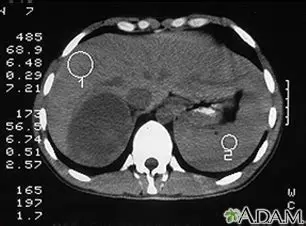

Cushing syndrome due to adrenal tumor